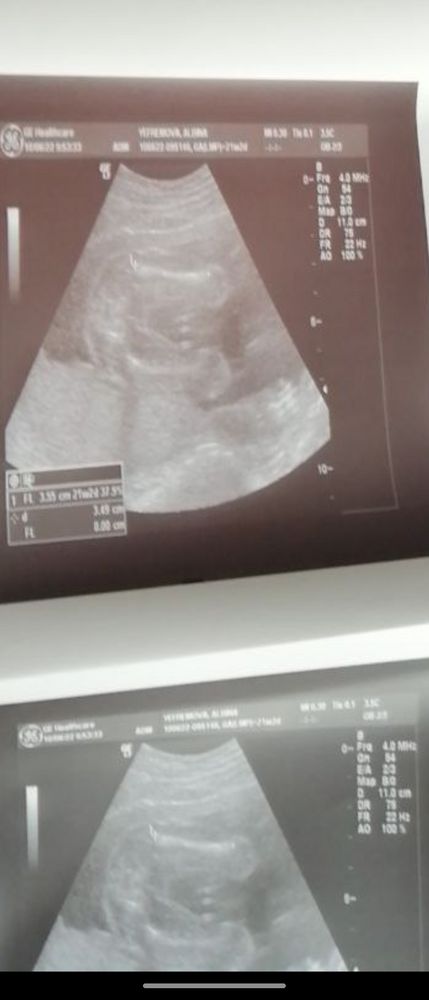

А мне не подскажите?😃 Изображение

11.06.2024

Девочка 💖 👧

10.06.2022

Да, девочка.

Девочка

Да девочка 👧